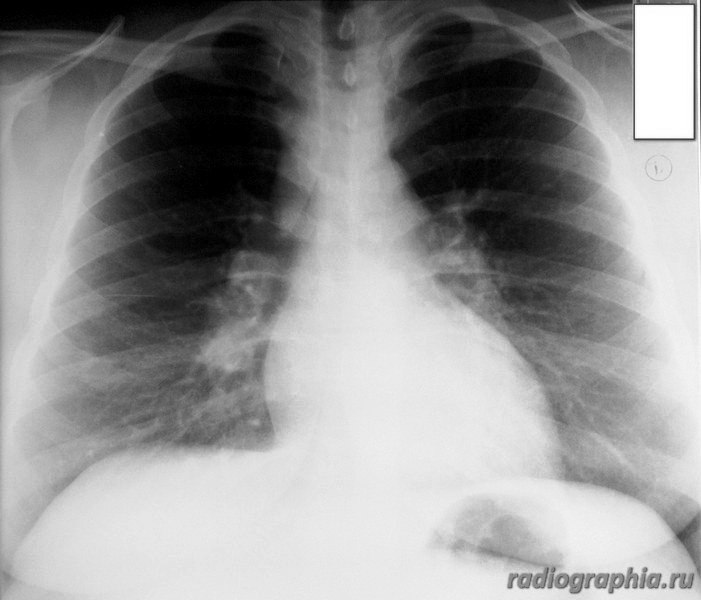

Рентгенография ОГК. Женщина средних лет.

интересует предыдущая рентгенодокументация (если есть :lol: ), анамнез заболевания. На момент осмотра больше данных за расширение легочных артерий , возможно начальные рентгенпризнаки развивающегося идиопатического легочного фиброза.Саркоидоз со стопроцентной уверенностью тоже исключать не стала бы.

Расширение верхнего средостения, широкие корни. У пациентки диагностирована лимфома. Была выполнена медиастиноскопия с забором лимфатических узлов на морфологию.